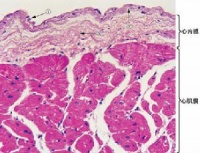

心肌细胞与骨骼肌的结构基本相似,也有横纹,但在结构上具有以下几个特征:

①心肌细胞为短柱状,一般只有一个细胞核,而骨骼肌纤维是多核细胞。心肌细胞之间有闰盘结构。该处细胞膜凹凸相嵌,并特殊分化形成桥粒,彼此紧密连接,但心肌细胞之间并无原生质的连续。心肌组织过去曾被误认为是合胞体,电子显微镜的研究发现心肌细胞间有明显的隔膜,从而得到纠正。心肌的闰盘有利于细胞间的兴奋传递。这一方面由于该处结构对电流的阻抗较低,兴奋波易于通过;另方面又因该处呈间隙连接,内有15~20埃的嗜水小管,可允许钙离子等离子通透转运。因此,正常的心房肌或心室肌细胞虽然彼此分开,但几乎同时兴奋而作同步收缩,大大提高了心肌收缩的效能,功能上体现了合胞体的特性,故常有“功能合胞体”之称。

②心肌细胞的细胞核多位于细胞中部,形状似椭圆或似长方形,其长轴与肌原纤维的方向一致。肌原纤维绕核而行,核的两端富有肌浆,其中含有丰富的糖原颗粒和线粒体,以适应心肌持续性节律收缩活动的需要。从横断面来看,心肌细胞的直径比骨骼肌小,前者约为15微米,而后者则为100微米左右。从纵断面来看,心肌细胞的肌节长度也比骨骼肌的肌节为短。

③在电子显微镜下观察,也可看到心肌细胞的肌原纤维、横小管、肌质网、线粒体、糖原、脂肪等超微结构。但是心肌细胞与骨骼肌有所不同;心肌细胞的肌原纤维粗细差别很大,介于0.2~2.3微米间;同时,粗的肌原纤维与细的肌原纤维可相互移行,相邻者又彼此接近以致分界不清。心肌细胞的横小管位于Z线水平,多种哺乳动物均有纵轴向伸出,管径约0.2微米。而骨骼肌的横小管位于A-I带交界处,无纵轴向伸出,管径较大,约0.4微米。心肌细胞的肌质网丛状居中间,侧终池不多,与横小管不广泛相贴。总之,心肌细胞与骨骼肌细胞在形态和功能上均各有其特点。